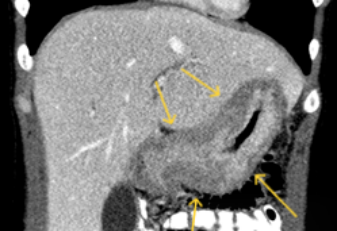

食管癌与胃癌:CT检查能清晰地显示食管壁或胃壁是否异常增厚,管腔是否狭窄。更重要的是,它能评估肿瘤是否突破了管壁,侵犯了周围的脂肪间隙、重要血管,同时可以评估周围淋巴结是否肿大。这就像在手术前进行一次“沙盘推演”,帮助外科医生规划手术路径和范围。例如,晚期胃癌在CT上可能表现为胃壁弥漫性增厚、僵硬,胃腔缩小,形成所谓的“皮革胃”。

图1 胃壁弥漫性异常增厚,胃腔变小,形成所谓的“皮革胃”